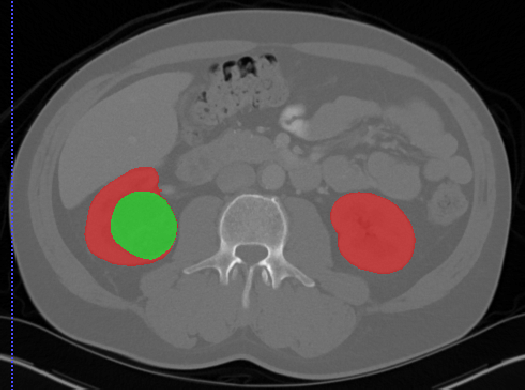

Kits19

| Kits19 | 肾脏/肾肿瘤 | 分割 |